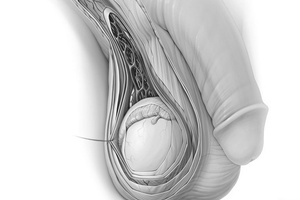

Сперматоцистит, или везикулит, – это воспалительное заболевание семенных пузырьков. Они находятся в области малого таза рядом с мочевым пузырем и стенкой прямой кишки и прикреплены к основанию предстательной железы. Семенные пузырьки – парный орган длиной 5 см, шириной 2 см и толщиной 1,5 см.

По структуре это трубчатые извилистые образования с множеством углублений и выводными протоками, соединенными с семявыносящим каналом.